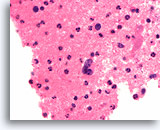

Afbeelding 15

Benigne, hyperplastisch/adenomatoïde nodule, schildklier FNA, celblok.

Dicht fibreus weefsel (niet actief desmoplastisch) met hemosiderine en beduidend atrofische, afgeplatte follikels kunnen worden waargenomen.

40X

Afbeelding 15

Benigne, hyperplastisch/adenomatoïde nodule, schildklier FNA, celblok.

Dicht fibreus weefsel (niet actief desmoplastisch) met hemosiderine en beduidend atrofische, afgeplatte follikels kunnen worden waargenomen.

40X